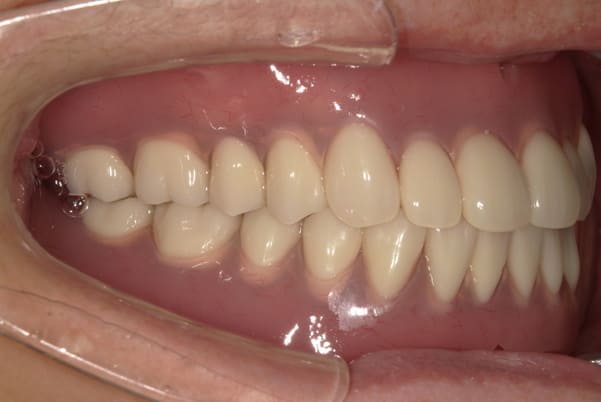

症例レポート[CASE.14]

上の歯を綺麗に治したい

- 性別・年齢

- 女性(50代)

- 主訴

- 上の歯を綺麗に治したい

- 治療

-

- 上顎ノンクラスプデンチャー

(チタン併用) - ジルコニアクラウン 9歯

- 治療期間

- 約7か月間

- 費用

- 上顎ノンクラスプデンチャー:33万円

(チタン併用) - ジルコニアクラウン:8.8万円×9歯

合計:112.2万円(税込)

左奥1本は虫歯で抜歯となりました。

歯がないところには、インプラント、ブリッジ、入れ歯の3つが選択肢となりますが、インプラントには抵抗がおありで、ブリッジの土台の奥歯は歯周病のため、できるだけ負担をかけたくないとのことで、最終的に入れ歯をご希望されました。

見える外側は金属がないバネを用い、見えない内側は違和感が小さく強度に優れ、入れ歯が安定するチタンを用いた部分入れ歯(特殊なノンクラスプデンチャー)

入れ歯では、犬歯にバネがかかりますが「入れ歯と分からないように」とのご希望で、外側のバネは審美性が高く、内側には強度が高く安定性がよく、また違和感が少ないチタンを併用したノンクラスプデンチャーで治療を行いました。

左上に入れ歯を装着されていますが、金属のバネがなく自然な口元に